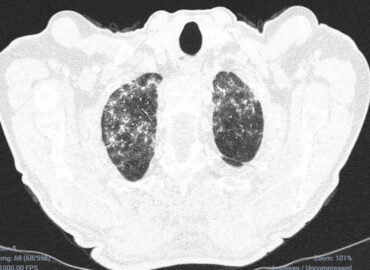

Paciente de sexo masculino de 68 años de edad, que consulta disnea CF III y tos con expectoración sanguinolenta […]